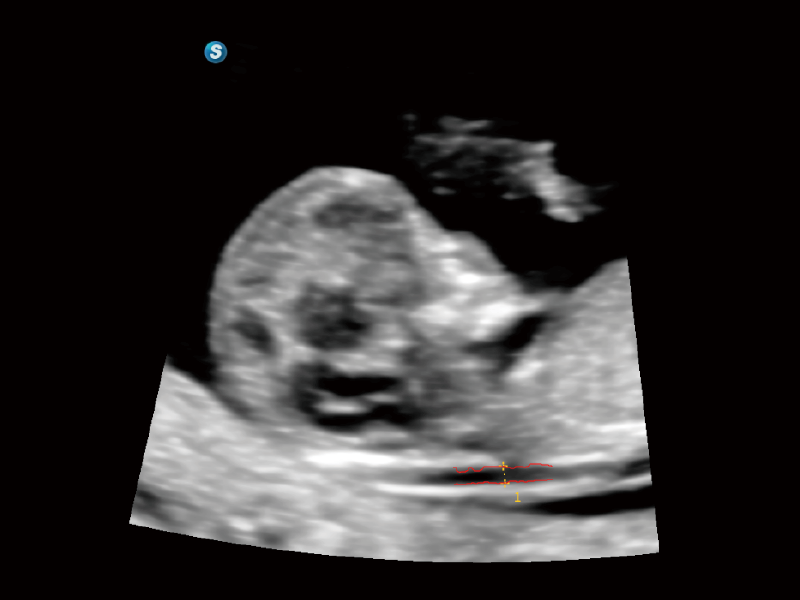

豐富的血流動(dòng)力學(xué)檢測(cè)技術(shù),可在不同醫(yī)療場(chǎng)景中高效捕捉血流信號(hào),助力臨床診療。

在傳統(tǒng)血流的基礎(chǔ)上優(yōu)化掃查和算法策略,能夠更好的抑制組織信息,提煉紅細(xì)胞運(yùn)動(dòng)信息,得到更高幀頻,高靈敏度和分辨率的血流信號(hào),還原更真實(shí)的血流動(dòng)力學(xué)。